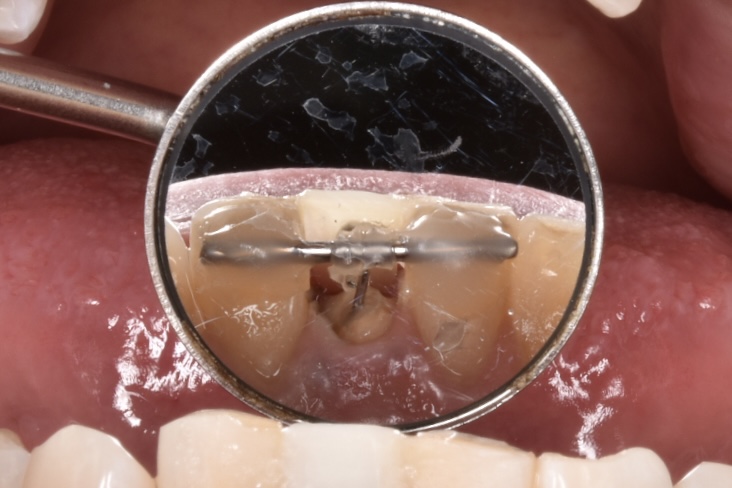

左右両隣は歯に1ミリの鋼線を使用して矯正用のゴムで折れてしまった歯を牽引しているところです。

裏側はこんな感じです。舌感は悪いですが、しばしの辛抱です。汚れが溜まりやすいので衛生面には注意が必要なのと、仮歯は張り付いているだけなので、とても取れやすいです。